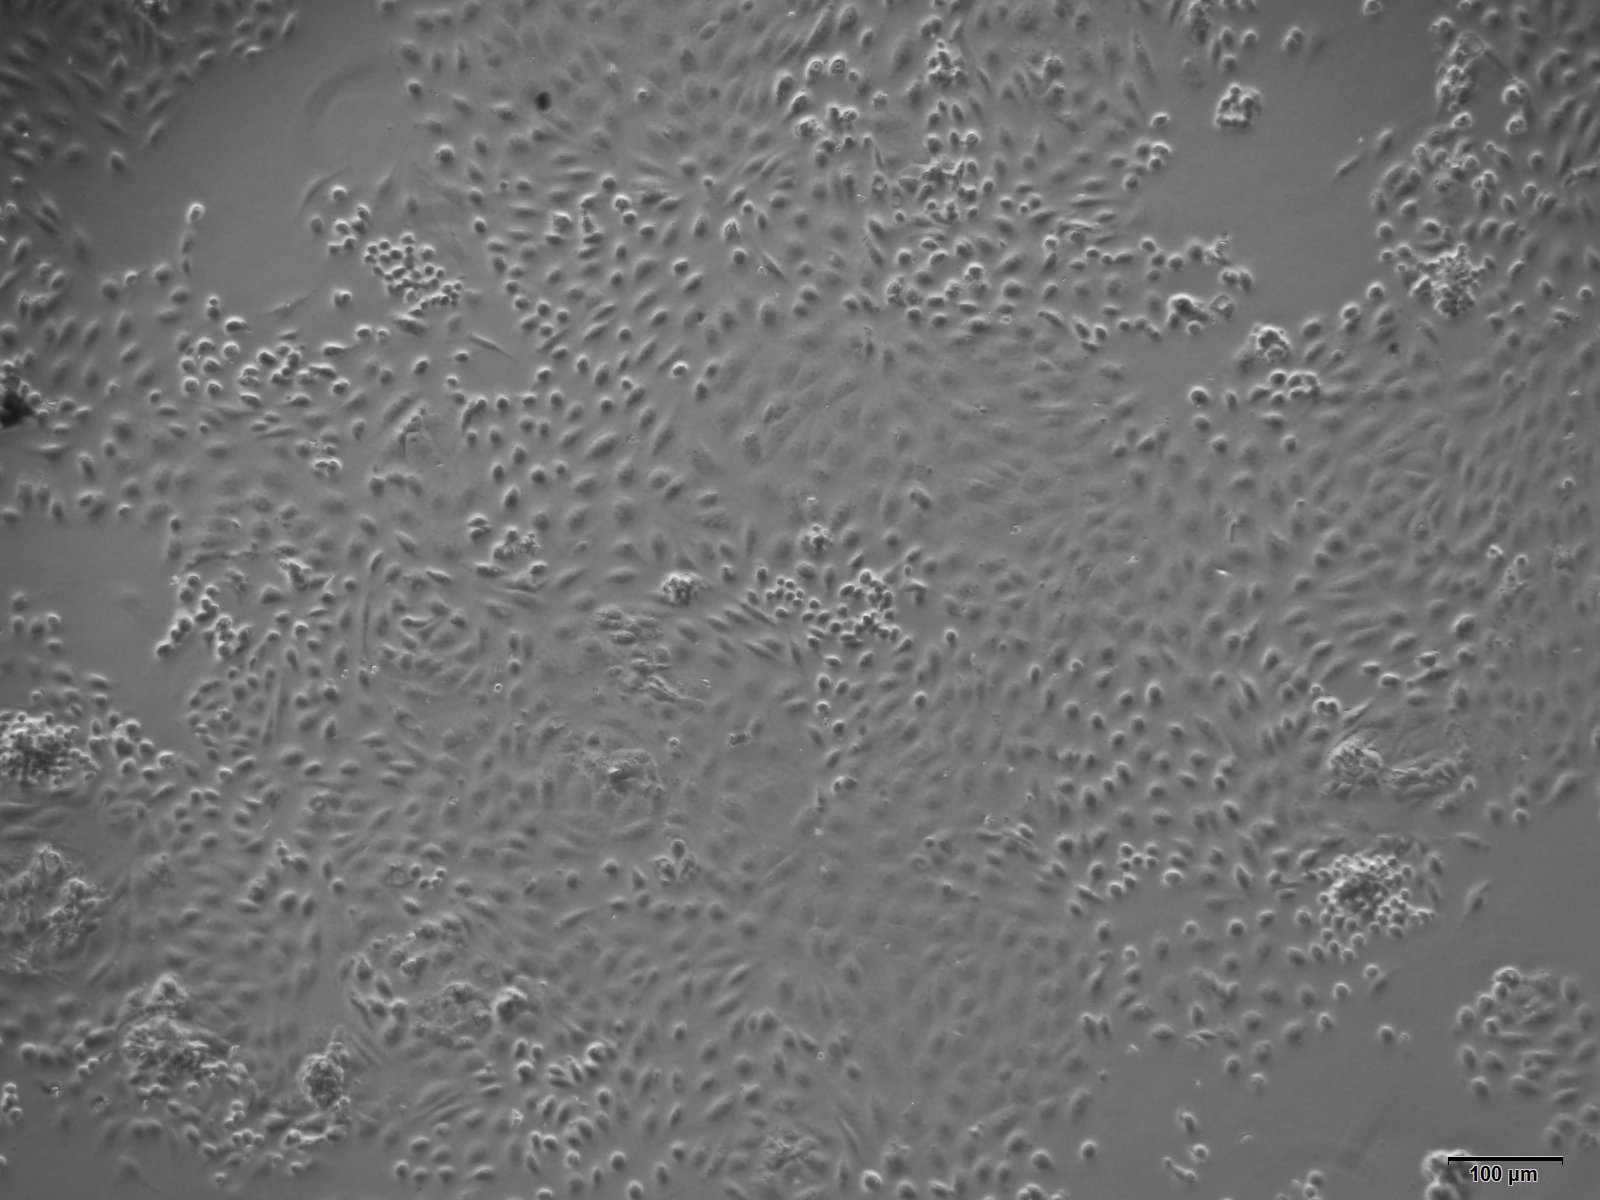

本公司生产的大鼠肾小球上皮细胞采用酶解法制备而来,细胞总量约为5×105/T25方瓶,CK-18、CK-19呈阳性,细胞纯度可达90%以上,且不含有HIV-1、 HBV、HCV、支原体、细菌、酵母和真菌等。